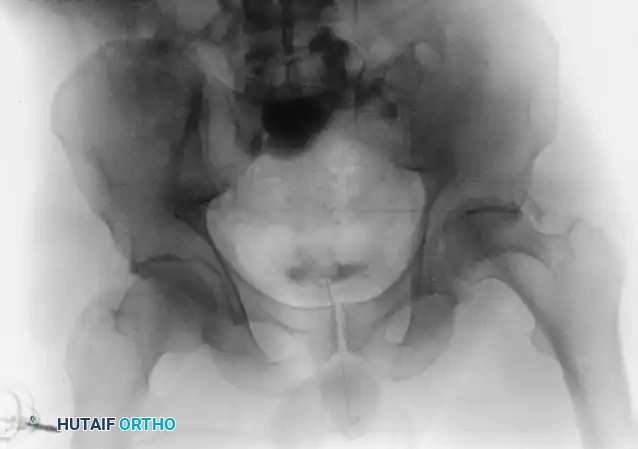

The evaluation begins with an Anteroposterior (AP) view of the pelvis, followed by the two Judet oblique views (Obturator Oblique and Iliac Oblique), taken at 45-degree angles.

Six fundamental radiographic landmarks must be identified on the AP radiograph to understand the fracture pattern:

1. Iliopectineal Line: Represents the anterior column.

2. Ilioischial Line: Represents the posterior column.

3. Radiographic Teardrop: Represents the medial wall of the acetabulum (anterior-inferior portion of the quadrilateral surface).

4. Roof of the Acetabulum: The superior weight-bearing dome.

5. Anterior Lip (Wall) of the Acetabulum.

6. Posterior Lip (Wall) of the Acetabulum.

Fractures traversing the anterior column disrupt the iliopectineal line, whereas posterior column fractures disrupt the ilioischial line.